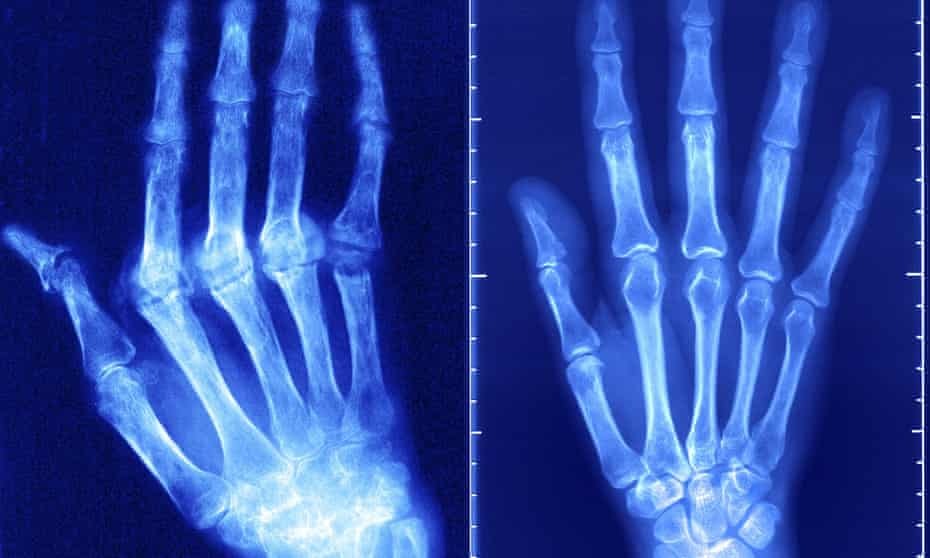

자가면역 질환은 제1형 당뇨병에서 류마티스 관절염, 염증성 장질환 및 다발성 경화증에 이르기까지 다양하다. 각각의 경우에 면역 체계는 혼선을 일으켜 감염원 대신 건강한 조직으로 향한다.

두 과학자 모두 염증과 붓기를 유발하고 심장을 포함한 다양한 장기에 손상을 입힐 수 있는 루푸스(lupus)뿐만 아니라 소아 지방변증을 포함한 질병들에 개개인의 감수성이 관련되어 있다고 강조했다.